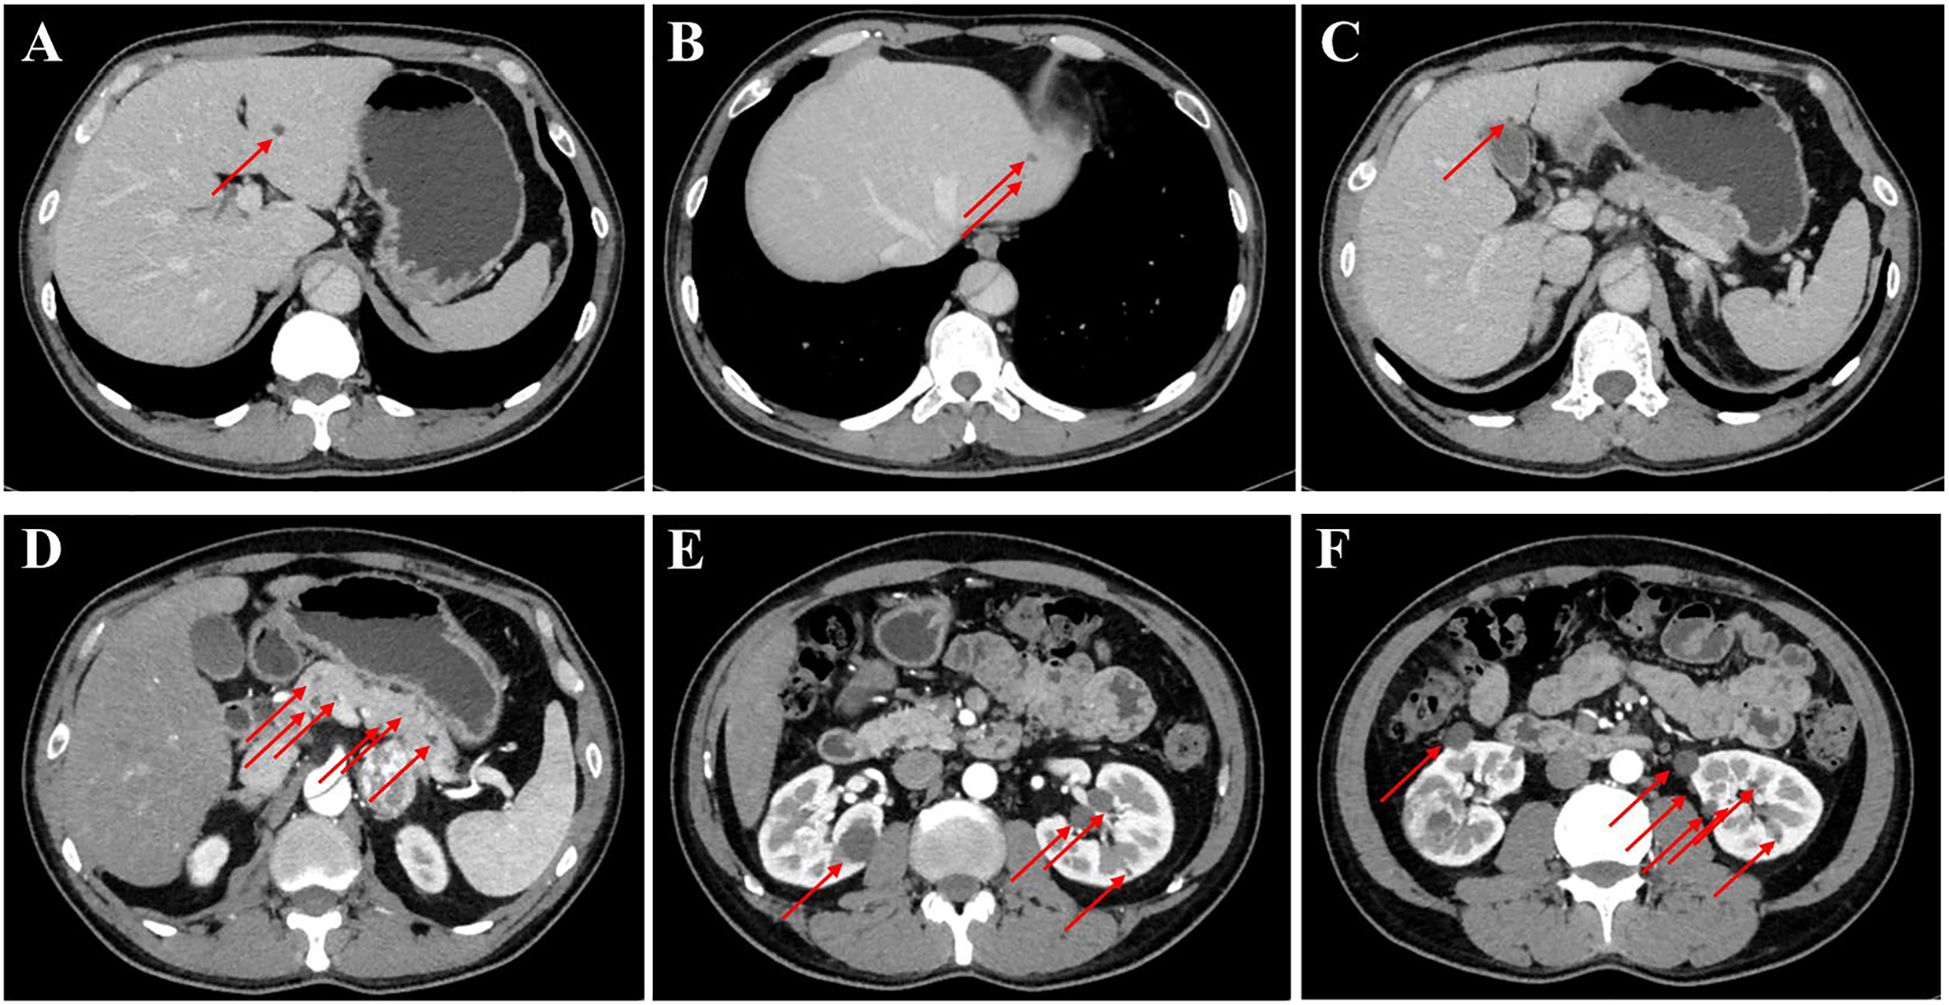

The patient was admitted to our department for further management of progressively enlarging left adrenal and right renal masses. A recent contrast-enhanced abdominal CT scan demonstrated substantial growth of the lesions, with the left adrenal mass measuring 4.1×3.5 cm and the right renal mass 3.5×3.5 cm (Figure 2). Upon adjusting the window width during image analysis, an additional renal mass measuring 1.3 × 1.4 cm was identified in the right kidney (Supplementary Figure 1). The imaging characteristics were consistent with pheochromocytoma and RCC. Subsequent serological evaluation revealed markedly elevated normetanephrine levels (Supplementary Table 1), which definitively confirmed the diagnosis of pheochromocytoma. Additionally, multiple hepatic, pancreatic and bilateral renal lesions were observed in the liver, pancreas and bilateral kidneys, radiologically consistent with hepatic hemangiomas and simple pancreas/renal/hepatic cysts (Figure 3, the number of renal cysts > 30).

Figure 3. Contrast-enhanced CT imaging of the upper abdomen in the patient. (A–C) Axial contrast-enhanced CT images of the liver and the arrow indicates the mass on the liver. (D) The contrast-enhanced CT image of the pancreas, revealing that the arrow indicates the mass on the pancreas. (E, F) The contrast-enhanced CT images of bilateral kidneys and arrows explain multiple cysts of both kidneys.